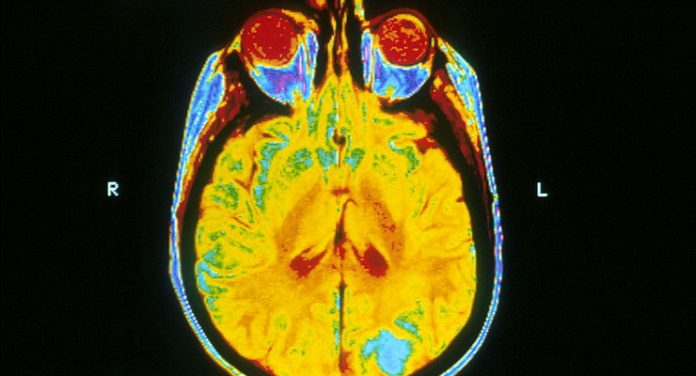

“Questa esplorazione ha evidenziato che gran parte del complesso groviglio di fibre interne può essere ricostruito con esattezza, utilizzando le sequenze di risonanza magnetica e i software di analisi dei centri di neuroimaging più avanzati, ma tante altre connessioni neurali generate dai software in realtà non esistono”, spiega Antonio Cerasa, ricercatore presso Ibfm-Cnr. “L’errore a cui vanno incontro tutti i centri di neuroimaging è di sottovalutare la complessa geometria delle fibre cerebrali, che proseguono parallele ma possono anche sovrapporsi, incrociarsi, cambiare improvvisamente direzione e struttura. Grazie a questo lavoro durato quasi due anni, oggi finalmente conosciamo i limiti di tale metodica e siamo quindi più vicini a descrivere interamente la complessa natura della mente umana in ogni sua forma. Per molti anni si era pensato che la nostra rete neuronale potesse essere ricostruita virtualmente dal neuroimaging con estrema precisione, lo studio evidenzia che questo non è completamente vero. Ad oggi le linee guida internazionali consigliano sempre di effettuare imaging multimodale con varie sequenze aggiuntive, che anche se allungano i tempi di esecuzione dell’esame, assicurano correttezza e sicurezza nei dati”.